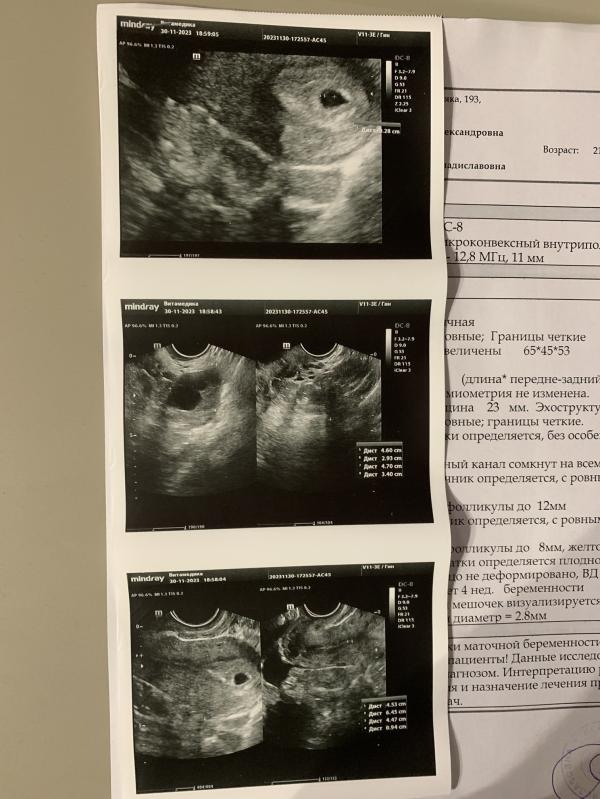

Хочу поделиться радостной новостью! Была сегодня на первом узи. Срок по месячным 6,2. Теплилась надежда увидеть эмбриончик, но пока не увидели, но и дпо у меня всего 22) Но увидели ПЯ и желточный мешочек😍❤️ Сказали, что срок примерно 4 недели. ПЯ - 9мм, ЖМ - 2,8мм

А еще! Шейка 45мм!!!! Это просто чудо какое то, несколько недель назад она была всего 17мм и я готовилась к ИЦН. Сейчас я просто молюсь, чтобы шейка так и была нормальной всю беременность🙏🏻